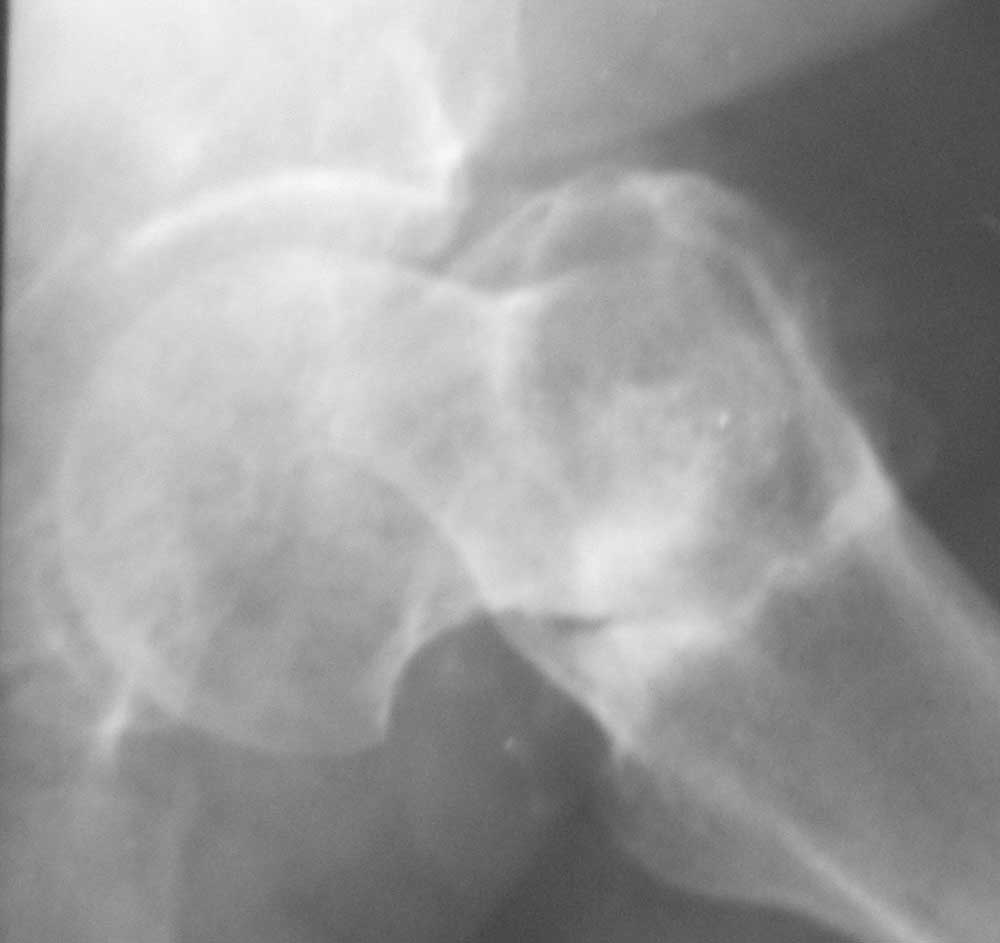

[Ortho] Ложный сустав базальной части шейки бедра

Больная 61 год. Травма 1 год назад – закрытый базальный перелом бедренной кости без смещения.

Перелом рентгенологически был диагностирован только через 6 недель (на первичных снимках

не визуализировался, КТ не проводилось, повторную травму отрицает). Проведен курс

консервативного лечения (ходьба на костылях без опоры на левую ногу до 4-х месяцев, ЛФК,

физиолечение и т.п.). В настоящее время передвигается при помощи костылей с незначительной

опорой на левую ногу. Больная страдает сахарным диабетом.

Возможные варианты лечения: 1) Тотальное эндопротезирование. 2) Ревизия ложного сустава, возможно костная пластика, МОС

углообразной пластиной 130, DHS, AFN.